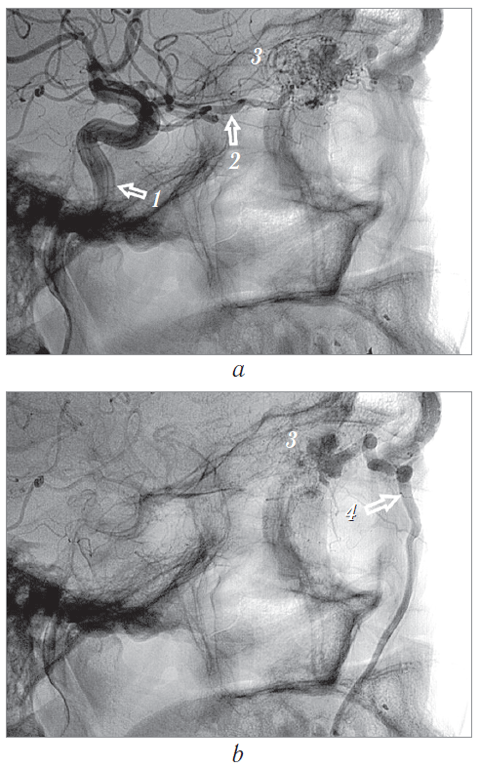

Согласно рекомендациям нейрохирурга выполнена селективная церебральная ангиография. В области правой орбиты выявлена интенсивная патологическая сосудистая сеть новообразования диаметром до 3 см, получающая кровоснабжение из правой глазной артерии с дренированием в правую лицевую вену (см. рис. 12, 17, a). Заключение: «Ангиографическая картина гиперваскуляризированного образования правой орбиты с питанием из ветвей правой глазной артерии».

Рис. 12. Ангиограмма правой внутренней сонной артерии и сосудов правой глазницы, сагиттальная проекция: а — артериальная и b — венозная фазы. 1 — правая внутренняя сонная артерия. Сосудистая сеть новообразования (а и b, 3) получает питание из расширенной глазной артерии (а, 2) с дренированием в правую лицевую вену (b, 4)

Fig. 12. Angiogram of the right internal carotid artery and the vessels of the right orbit, sagittal projection: a — arterial phase, b — venous phase: 1 – right internal carotid artery. The vessels of the neoplasm (а and b, 3) are fed from the dilated ophthalmic artery (а, 2) with drainage into the right facial vein (b, 4)

Катетеризирована правая внутренняя сонная артерия. Выполнена стандартная и ротационная ангиография. При стандартной субтракционной (рис. 13) и ротационной (рис. 14) ангиографии визуализируется выраженная собственная сосудистая сеть новообразования правой орбиты, источником которой является правая глазная артерия. Венозный отток осуществляется по варикозно расширенной дренирующей угловой вене, впадающей в лицевую вену.

Рис. 13. Субтракционная ангиограмма в боковой проекции: а — артериальная фаза; b — венозная фаза. 1 — правая внутренняя сонная артерия; 2 — глазная артерия; 3 — собственная сосудистая сеть новообразования; 4 — варикозно расширенное устье дренирующей вены; 5 — дренирующая лицевая вена

Fig. 13. Subtraction angiogram in lateral projection: а – arterial phase, b – venous phase. 1 – right internal carotid artery; 2 – ophthalmic artery; 3 – own vascular network of the neoplasm; 4 – varicose dilated drainage vein opening; 5 – draining facial vein